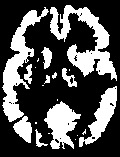

Accurate infarct segmentation in non-contrast CT (NCCT) images is a crucial step toward computer-aided acute ischemic stroke (AIS) assessment. In clinical practice, bilateral symmetric comparison of brain hemispheres is usually used to locate pathological abnormalities. Recent research has explored asymmetries to assist with AIS segmentation. However, most previous symmetry-based work mixed different types of asymmetries when evaluating their contribution to AIS. In this paper, we propose a novel Asymmetry Disentanglement Network (ADN) to automatically separate pathological asymmetries and intrinsic anatomical asymmetries in NCCTs for more effective and interpretable AIS segmentation. ADN first performs asymmetry disentanglement based on input NCCTs, which produces different types of 3D asymmetry maps. Then a synthetic, intrinsic-asymmetry-compensated and pathology-asymmetry-salient NCCT volume is generated and later used as input to a segmentation network. The training of ADN incorporates domain knowledge and adopts a tissue-type aware regularization loss function to encourage clinically-meaningful pathological asymmetry extraction. Coupled with an unsupervised 3D transformation network, ADN achieves state-of-the-art AIS segmentation performance on a public NCCT dataset. In addition to the superior performance, we believe the learned clinically-interpretable asymmetry maps can also provide insights towards a better understanding of AIS assessment. Our code is available at https://github.com/nihaomiao/MICCAI22_ADN.